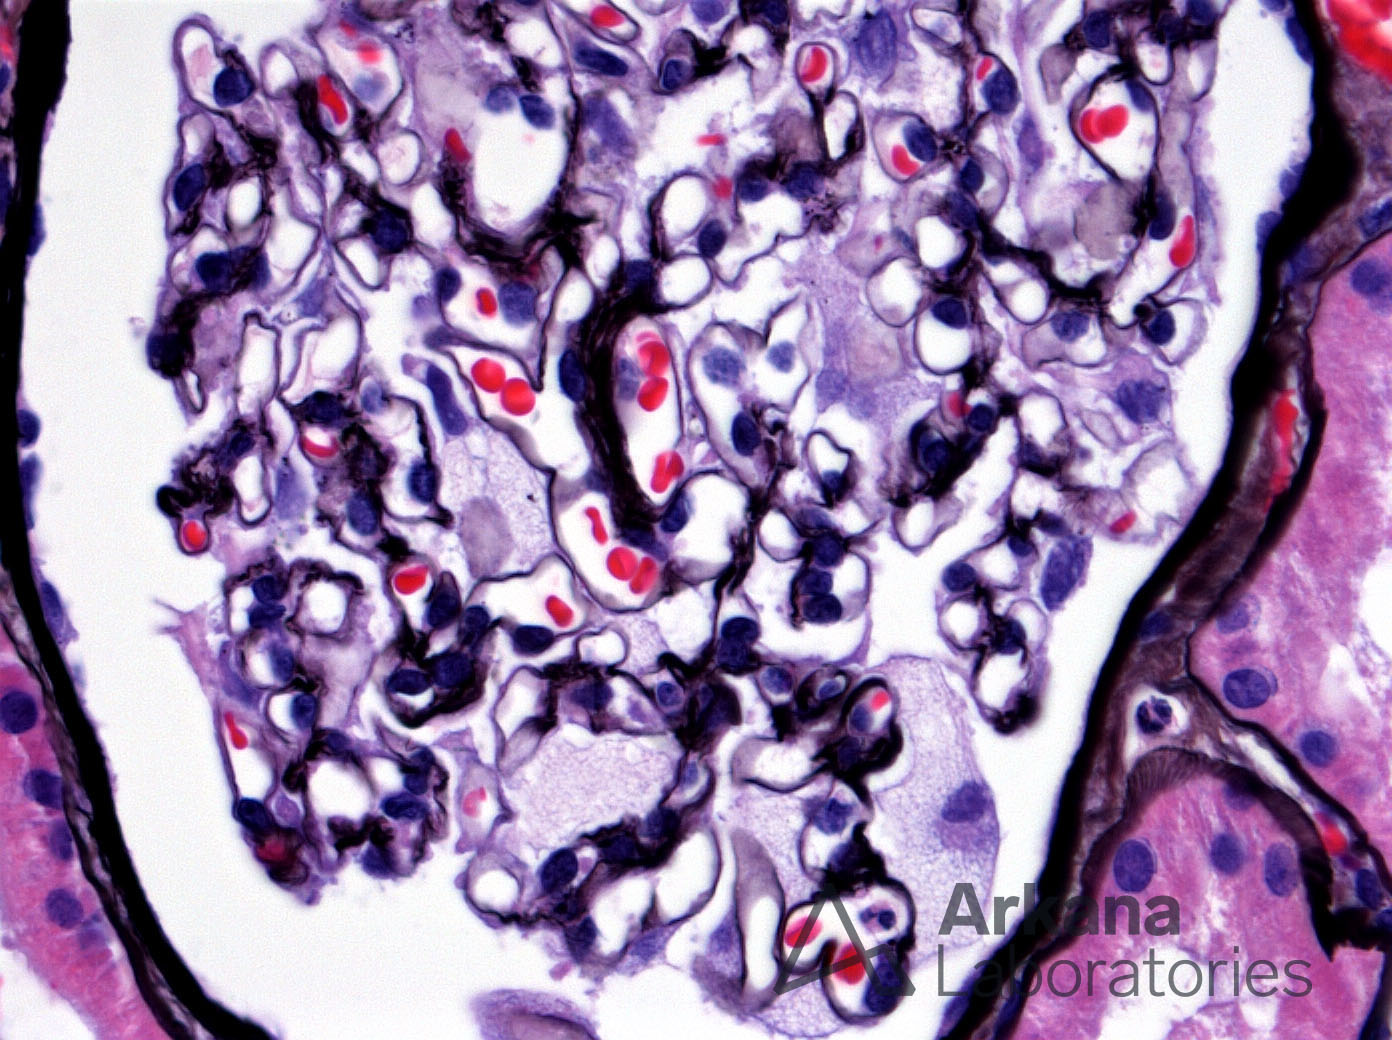

Foamy Podocytes in Fabry Disease_2